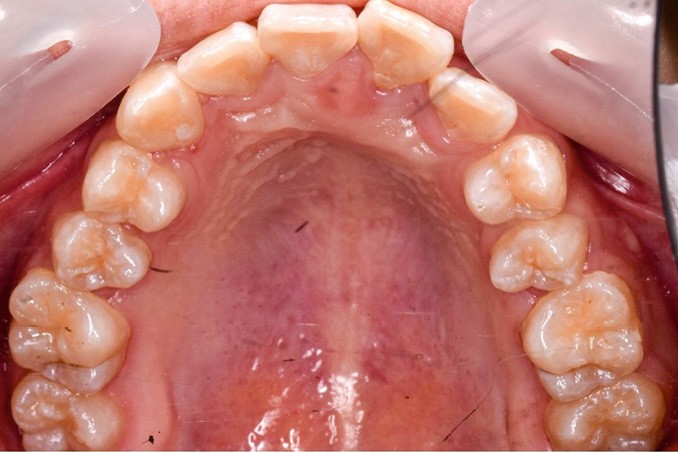

Une patiente âgée de 12 ans se présente en consultation, motivée par la position de son incisive centrale maxillaire, décrite comme « en avant », marquée par une dyschromie et une mobilité de grade 2 selon Muhlemann. L’examen clinique montre l’absence de 23 sur l’arcade, une dysharmonie dents-arcade marquée, un surplomb accentué, et une déviation des milieux inter-incisifs, conséquence du comblement spontané de l’espace de 23. L’ensemble s’inscrit dans un contexte de Classe I d’Angle molaire. L’orthopantomogramme révèle l’inclusion de 23, associée à une résorption radiculaire étendue aux deux tiers de 21. La 22 ne présente aucune altération visible.

La patiente, de profil normodivergent, présente une Classe I squelettique sans troubles fonctionnels (fig. 1-8).